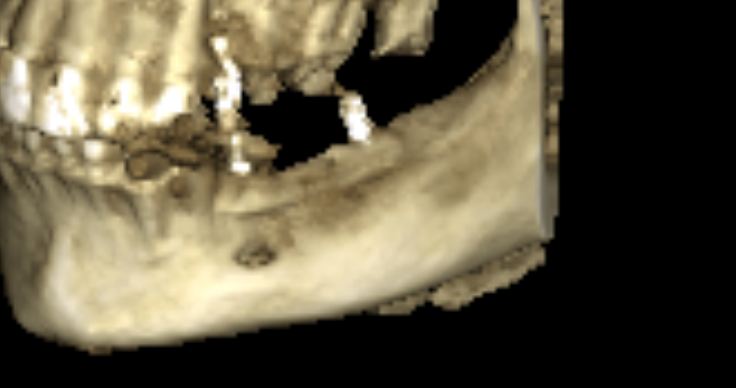

Простой. Надежный. Дешевый. Способ остеопластики.